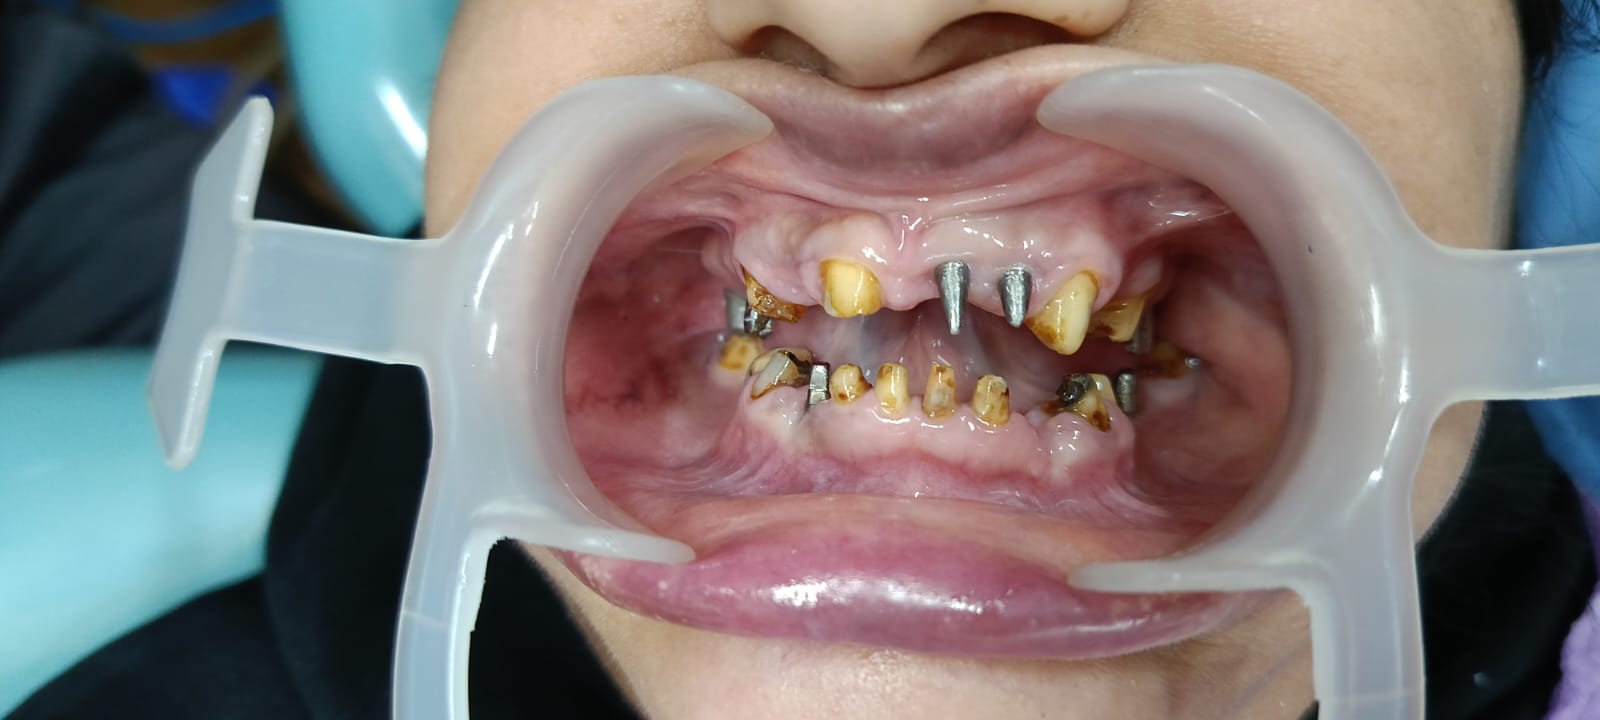

Apollo Spectra Hospital specializes in dental implants, offering a reliable and effective solution for tooth loss. Our advanced implant services are designed to restore function and aesthetics, enhancing patients' quality of life.

Dental implants are titanium posts surgically placed into the jawbone to serve as artificial tooth roots. This procedure provides a strong foundation for replacement teeth, ensuring stability and durability. Our skilled oral surgeons conduct thorough assessments to determine the suitability of implants for each patient, taking into consideration bone density, oral health, and individual needs.

The implant process typically involves several stages, starting with the surgical placement of the implant, followed by a healing period during which the implant fuses with the bone—a process known as osseointegration. After sufficient healing, custom-made crowns are affixed to the implants, restoring both function and natural appearance. This approach allows patients to enjoy improved chewing ability and confidence in their smiles.